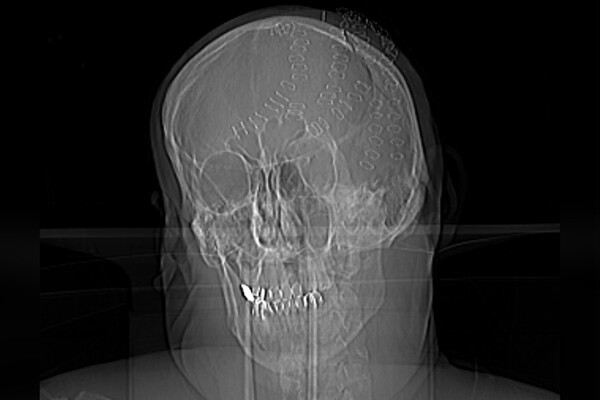

Во Владивостоке врачи Тысячекоечной больницы спасли 50-летнего мужчину с раздробленным черепом в результате удара топором. Об этом рассказали в пресс-службе медицинского учреждения.

Пациент получил бытовую травму на острове Попова, откуда его экстренно эвакуировали на катере. Несмотря на сложность эвакуации, через три часа после инцидента, нейрохирурги приступили к операции. Мужчине диагностировали рубленные раны головы, множественные оскольчатые и вдавленные переломы теменных костей, травматическое субарахноидальное кровоизлияние, ушиб головного мозга. Медики отметили, что к моменту его поступления в стационар требовалась срочная операция.

«Из-за обширной потери крови он впал в геморрагический шок, что угрожало его жизни. Врач-нейрохирург Никита Барышников внимательно изучил повреждения и начал обработку ран, удаление вдавленных фрагментов костей черепа, а также остановку кровотечения из поврежденных сосудов», — рассказали в пресс-службе.

Медики несколько часов собирали мужчине череп по частям, операция завершилась успешно.